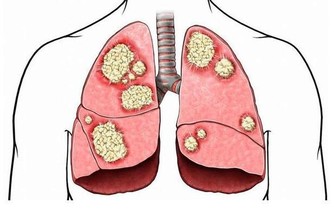

最後肛門也有這保護腸胃的功能,很多人可能有些納悶肛門跟腸胃有什麼關係,其實肛門和我們的腸胃是連著的,也在為我們的腸胃阻擋一些外來細菌,因此如果肛門不及時清潔產生了細菌,久而久之就會導致細菌進入到腸道內部,引起腸道疾病。